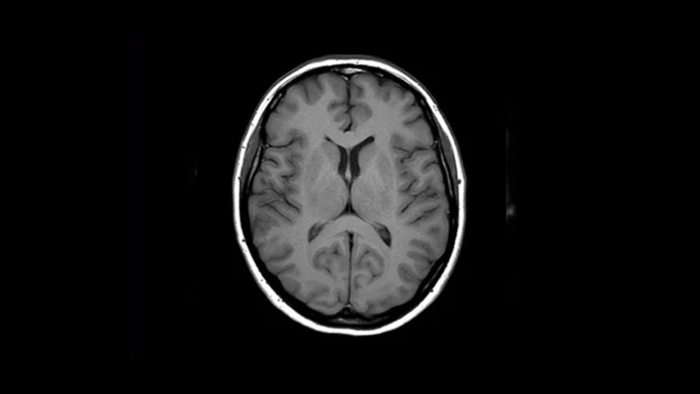

La nouvelle réalité clinique : confiance et rapidité

Vitesse Accélérez vos acquisitions jusqu’à 50 %. Gagnez du temps dans votre planning ou réalisez des séquences supplémentaires pour compléter le diagnostic.2

Confiance diagnostique Jusqu’à 60 % de résolution spatiale supérieure, dans le même laps de temps4, notamment pour les explorations ostéoarticulaires.